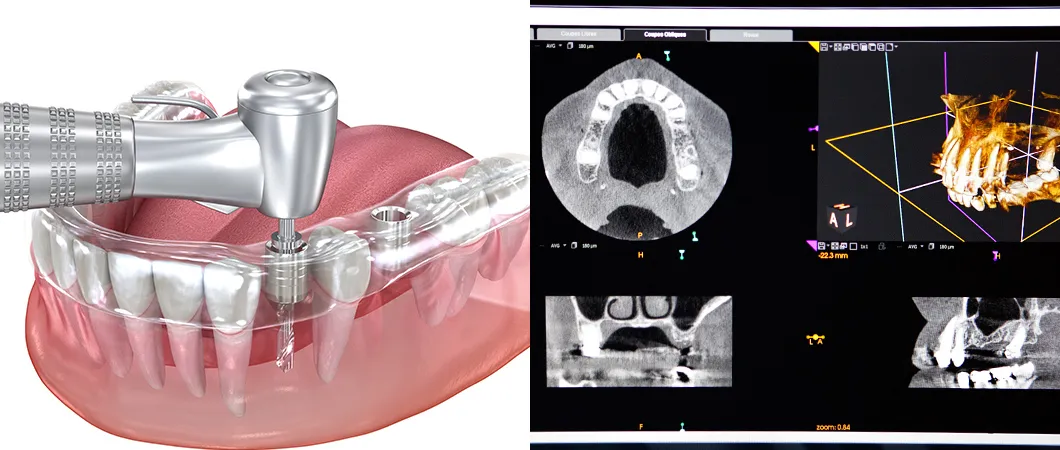

インプラント治療では、インプラント(人工歯根)を顎骨に埋め込む手術が欠かせません。安全性を充分に配慮したインプラント埋入手術をご提供するために、当院ではガイデッドサージェリーシステムを活用しています。

まず、歯科用CTで撮影した口腔内や顎骨の3D画像をもとに、専用のソフトを使ってインプラント埋入手術をシミュレーションします。これに基づいてサージカルガイドという手術用のテンプレートを作製し、それを利用してインプラントを埋め込む治療法です。

実際の手術では、サージカルガイドに沿って的確な位置にインプラントを埋め込みます。神経や血管などを傷つけるリスクを大幅に抑えられ、安全・安心なインプラント治療を実現できるのです。